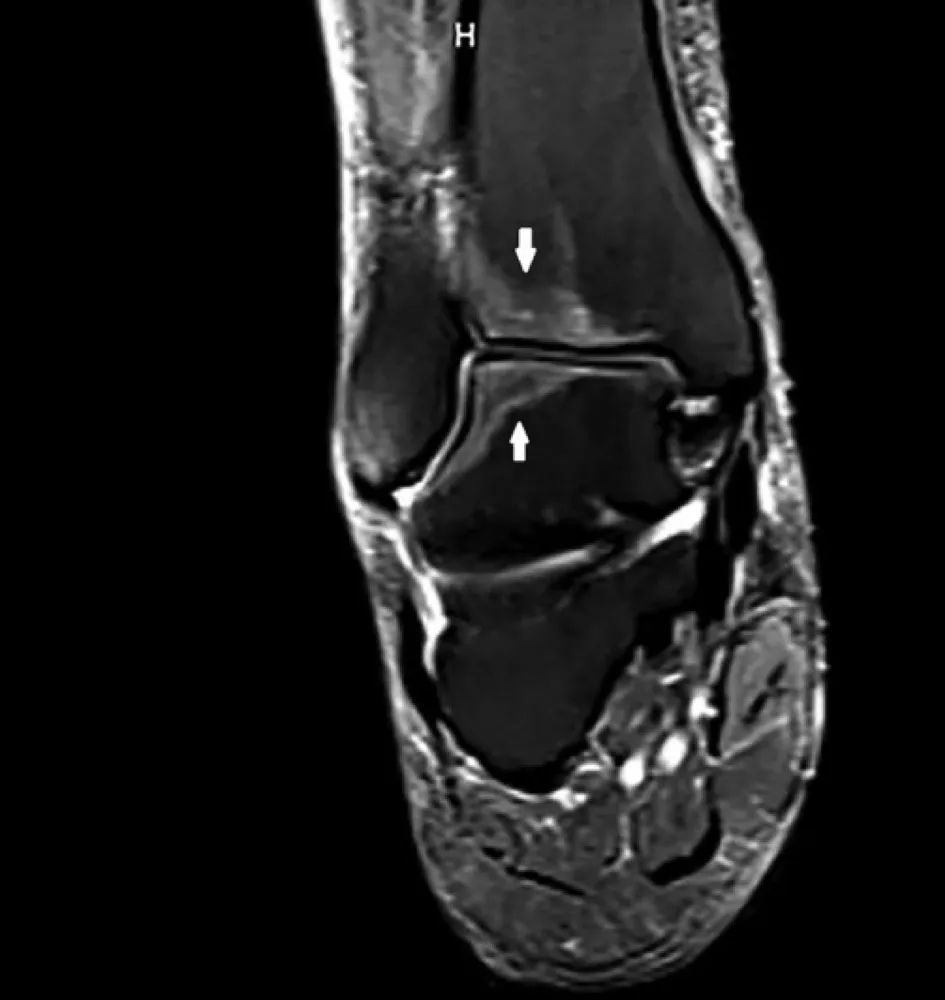

Uma causa incomum de hematúria glomerular intermitente!

Hematúria pós infecção, caso clínicos para auxiliar no entendimento de causas glomerulares comuns e raras...